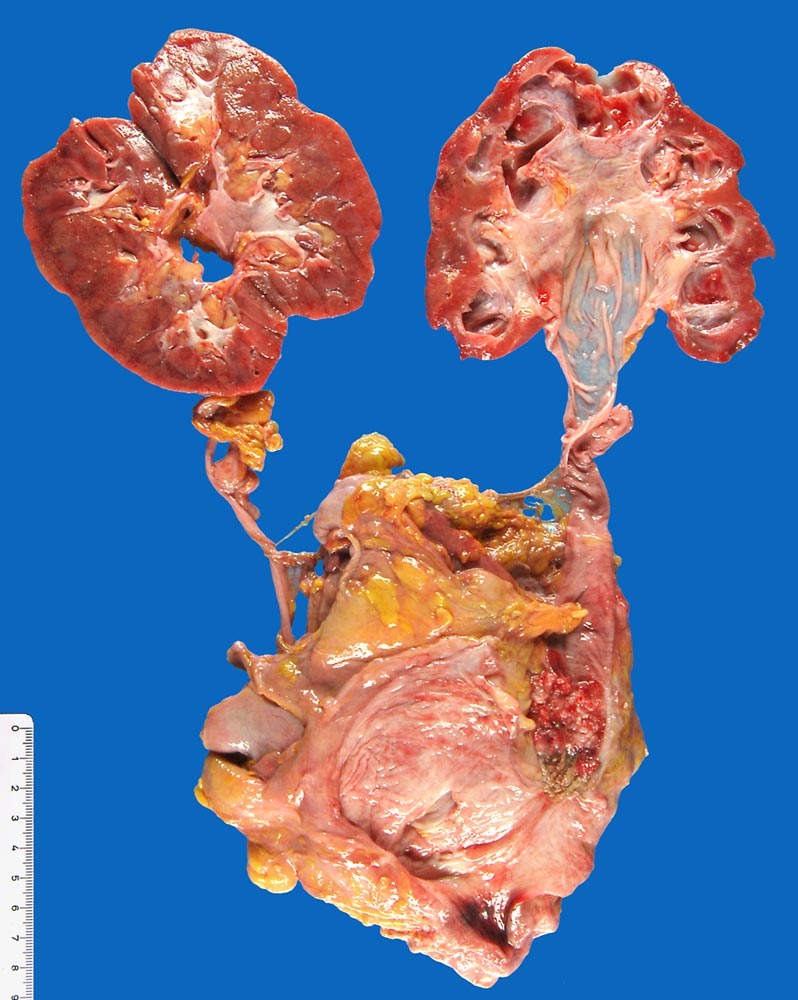

PathoPic – image database / PathoPic ID 9905 - Invasives papilläres Urothelkarzinom mit Hydronephrose

Invasives papilläres Urothelkarzinom mit Hydronephrose

Papillärer Tumor im distalen Ureter. Distal davon Richtung Harnblase ist der granulierende Ulkusgrund der transurethralen Resektion vor 4 Monaten sichtbar. Hydronephrose und Hydroureter auf der Seite des ureteralen Tumors.

Aktuell: Reste des wenig differenzierten Urothelkarzinoms im distalen Ureter. Ausdehnung: 10mm, rpT2a G3 pN2 M1 L1 V1.

Transurethrale Resektion eines wenig differenzierten papillären Urothelkarzinoms vor 1 Jahr pT1. Resektion eines Rezidivs des Karzinoms vor 4 Monaten.